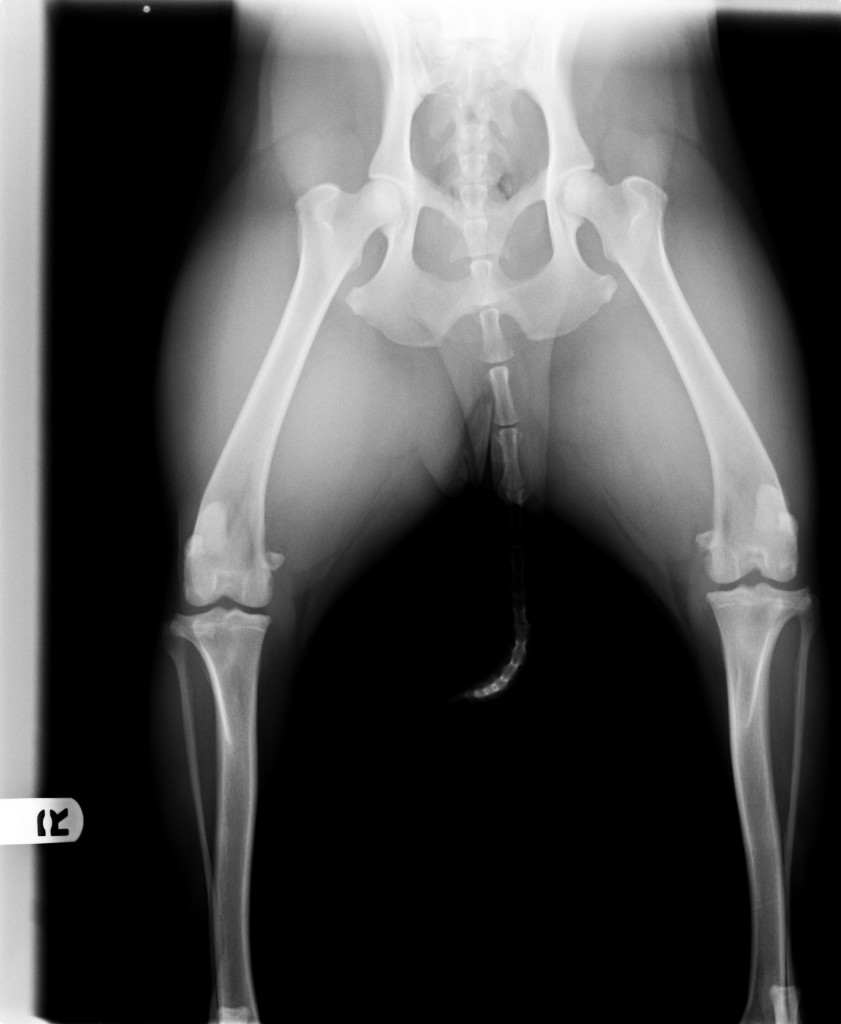

Audrey’s X-rays

Here are the X-Rays from Audrey’s knee surgery